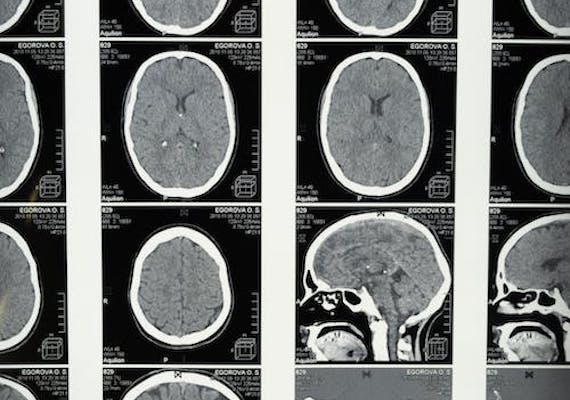

Another experimental Alzheimer’s drug has been shown to slow patients’ worsening conditions, researchers reported Monday. The American drug company Eli Lilly said it is seeking U.S. Food and Drug Administration (FDA) approval for the drug donanemab. If approved, it would be the second Alzheimer’s treatment for delaying the disease. Alzheimer’s affects the brain and causes memory loss and dementia. The FDA approved Leqembi, from Japanese drugmaker Eisai, earlier this month. “Finally there’s some hope, right, that we can talk about,” Lilly’s Dr. John Sims told reporters Monday at the Alzheimer’s Association International Conference in Amsterdam, the Netherlands. The drug does not cure the disease. Instead, it slows its progression by about four to seven months. But Sims noted that “it doesn’t mean you can’t have very meaningful treatments for patients.” Eli Lilly published the full results of its study of 1,700 patients in the Journal of the American Medical Association. It also presented its results at the Alzheimer’s conference.